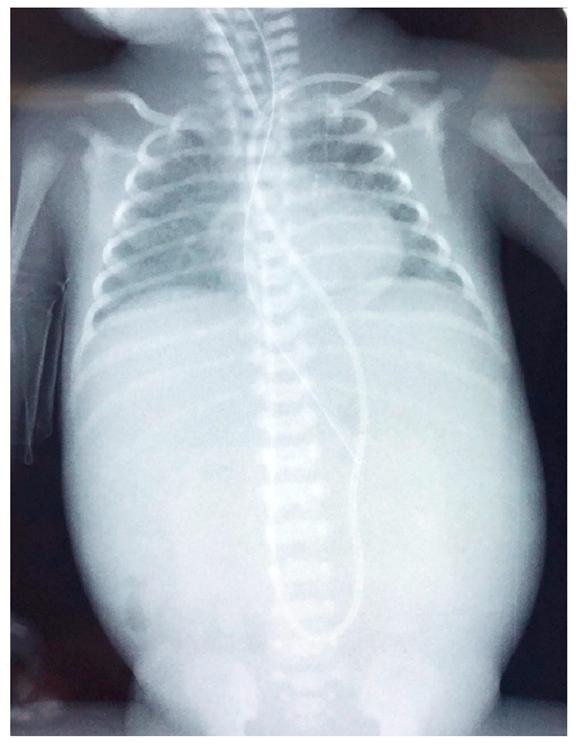

The neonate was then stabilized, and ultrasonography was performed in order to differentiate the possible causes of blood loss. No IVH was confirmed by cranial ultrasonography, while abdominal ultrasonography depicted a hypoechogenic intrahepatic irregular lesion on the right lobe (3.4 cm × 1 cm) (Figure 8a), with hematoma being the possible diagnosis from the radiologist. Chest and abdominal radiography (Figure 9a) showed an abnormal position of UVC, so it was removed. On the following radiography (Figure 9b) air in the branches of right portal vein and hepatic parenchyma was noted (as shown in Figure 9b).

Figure 9.

(a) Chest and abdominal radiography depicting the abnormal position of umbilical venous catheter in the liver (red arrowhead); and (b) chest and abdominal radiography depicting air in the branches of right portal vein and hepatic parenchyma (red arrowhead).

The following days the neonate remained hemodynamically stable, with no evidence of new blood loss throughout the rest of her stay in the NICU. Subsequent abdominal ultrasound showed a gradual resolution of the intrahepatic lesion. Three months after the initial scan, at the right lobe of the liver, multiple hepatic calcific deposits (1 cm × 1 cm) were demonstrated (Figure 8b). The infant was discharged home on the 72nd day of life. To this date, she remains well, albeit the sequelae of his prematurity.